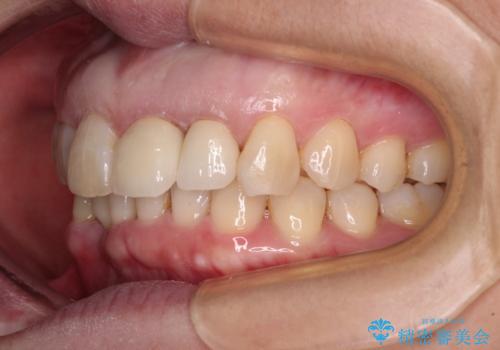

- 下顎前歯が抜けそうとのことで来院された患者様です。

初診の状態ではすぐにでも抜けそうな状態で、インプラントによる補綴治療を行うこととしました。

インプラント治療に際し、前歯の叢生に対する矯正治療を提案したところ、興味を持たれたので、インビザライン・ライトによる矯正治療を行うこととしました。

抜歯後にスペースができると恥ずかしいため、抜歯した歯を接着剤で固定した上で矯正治療を行い、その後インプラントやオールセラミッククラウンの装着を行うこととしました。